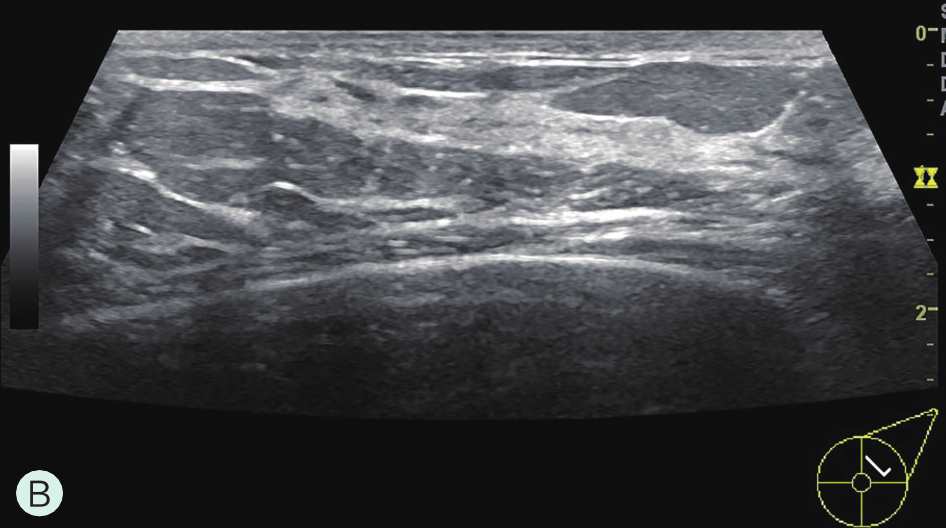

图1-3-2 乳腺超声不同乳腺密度

A.脂肪型;B.散在致密型;C.不均匀致密型;D.极度致密型